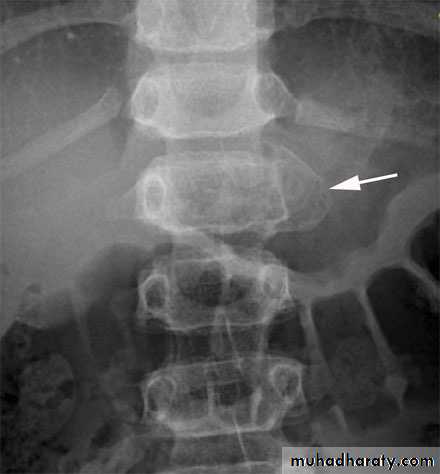

Chance fracture

Fracture dislocation